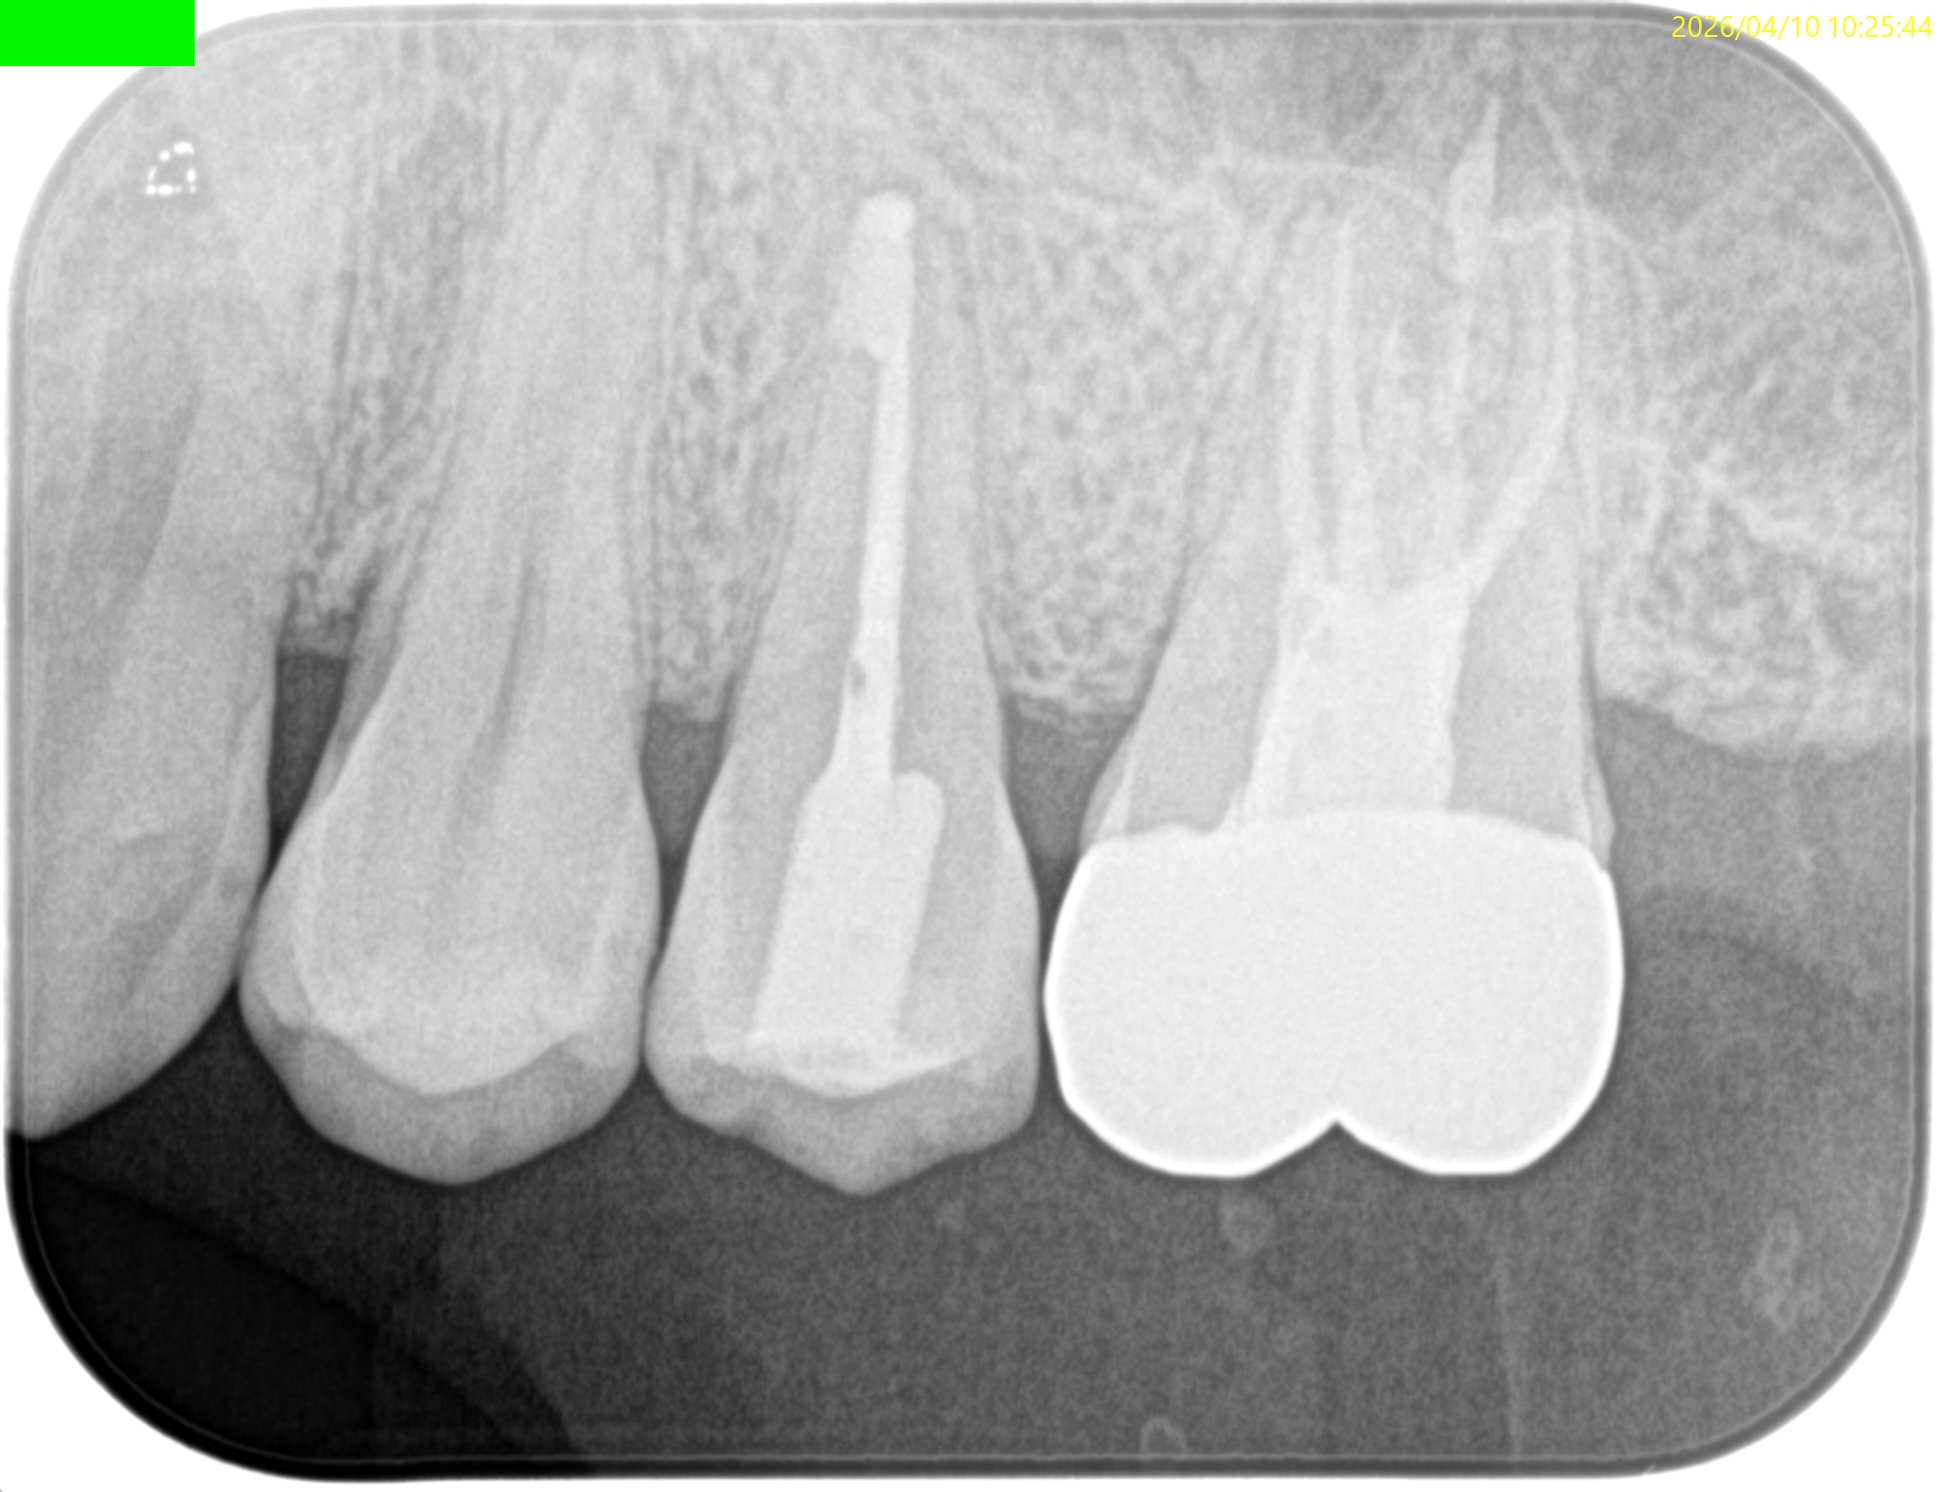

#13 Intentional Replantation 1yr recall(2026.4.10)

1年前と比較した。

歯槽骨の欠損部分は完治した。

打診時のアンキローシス音もない。

ということで、臨床症状もないのでこの日で終診とさせていただいた。